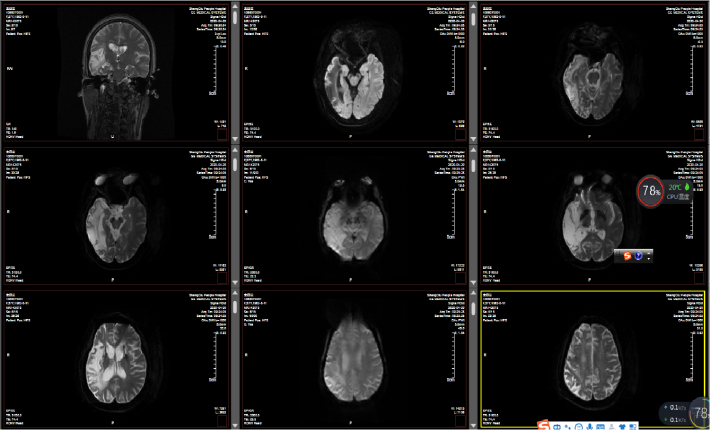

入我院后头颅MR

病史特点:1.既往高血压病史,有多次脑梗死病史,本次CTA及DSA回示右侧颈总动脉及颈内动脉分叉处重度狭窄,狭窄率≥95%;2.头颅PWI回示:提示存在低灌注情况;3.MR斑块分析:右侧颈内动脉分叉处管腔重度狭窄,斑块内出血,考虑易损斑块;4.NIHSS评分较低,无明显瘫痪 。

从以上分析:患者有一定的手术适应症,但通过DSA造影发现右侧大脑中动脉已闭塞,即使行支架植入术患者获益不大,且存在高灌注风险;患者DSA造影显示弓上血管发育异常,双侧颈总动脉共干,双侧椎动脉分别起始于双侧锁骨下动脉,右侧迷走锁骨下动脉,手术有一定难度; 虽然患者右侧大脑中动脉已闭塞,但无明显肢体瘫痪,侧枝循环已建立,考虑慢性闭塞可能性大,开通后获益不大,但存在较大风险,手术弊大于利,建议保守治疗。